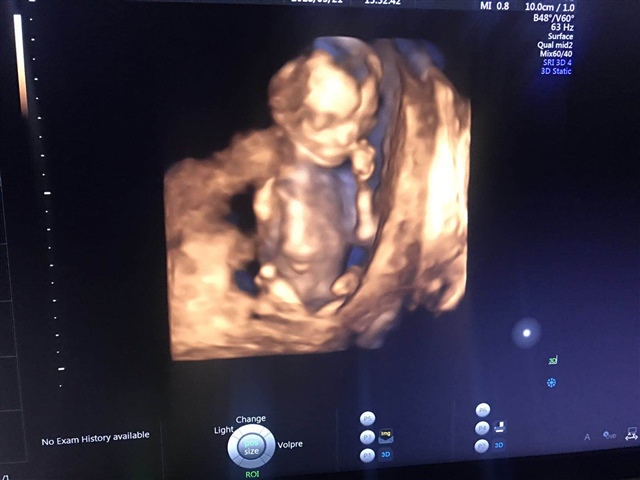

孕24周+2天

不会